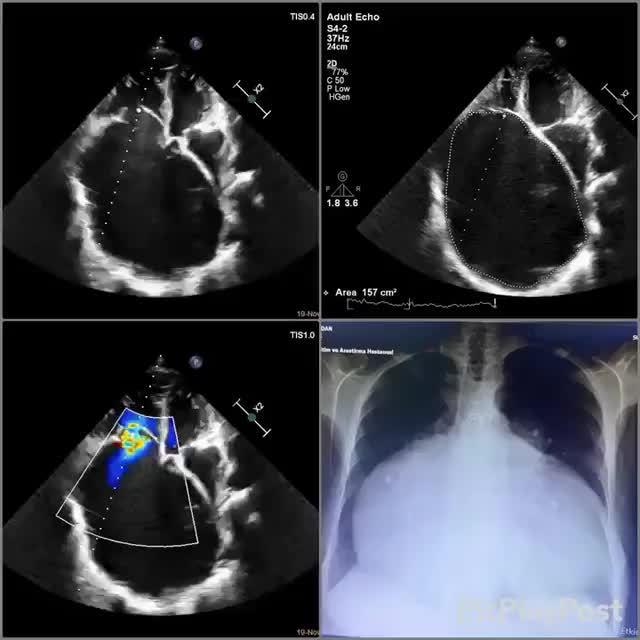

右心室肥大,太可怕了,单单高血压恐怕难以达到这样的程度

右心室肥大心电图特征

右心室增大